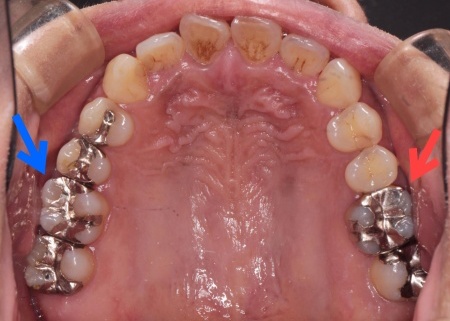

50代女性銀歯の下の虫歯を除去しセラミックで修復したケース

レントゲン像で金属の下に虫歯があり、患者さんは入れ替えを強く希望されました。

特に審美的な要求をされたため、セラミック修復の説明をし、治療の同意を得ました。